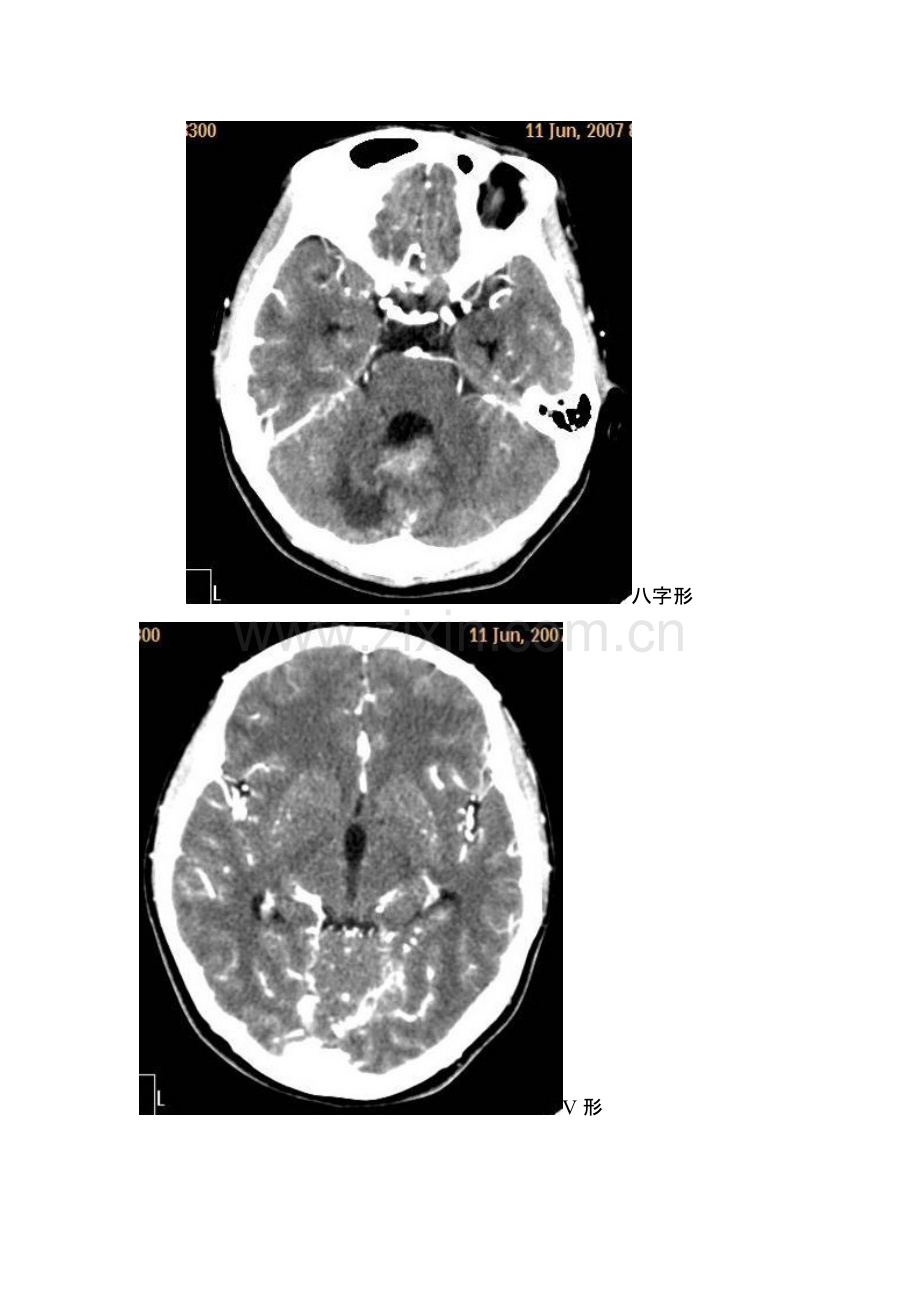

影响解剖学影响解剖学 知识点知识点 学期结束了,在此把学的知识整理一下,这里有老师讲课中强调的考试重点,也有以后到临床要注意的问题。这里不安书本的章节顺序 一,中枢神经系统 1、颅中窝:蝶鞍两侧从前至后依次为眶上裂、圆孔、卵圆孔、棘孔。(眶上裂通过动眼神经、滑车神经、三叉神经的眼神经以及外展神经,圆孔通过上颌神经,卵圆孔通过下颌神经,棘孔通过脑膜中动脉)2、脑干的组成:中脑、脑桥、延髓。3、大脑半球比较重要的三个沟:中央沟、外侧沟、顶枕沟。4、颅缝的封合时间是 3050 岁,闭合顺序是矢状缝、冠状缝、人字缝。5、鞍上池的形状有五边形和六边形,五边形时后方为脑桥上缘,六边形时正后方为脚间池,脚间池向后通环池,四叠体池(呈“W”型)。脚间池和环池环绕的脑组织是中脑。6、小脑幕的形态:有八字形、V 形、Y 形 八字形 V 形 Y 形 Y 形 7、大脑半球从外向里的结构:脑皮质、脑髓质、基底核、第三脑室 8、大脑大动脉环(基底动脉环):由前交通动脉、双侧大脑前动脉起始部、两侧颈内动脉、两侧后交通动脉及两侧的大脑后动脉起始部构成,又称 Willis 环.二、头颈部 9、中耳的结构:包括鼓膜、咽鼓管、鼓室、听小骨、乳突窦,乳突小房。10、内耳从前内到后外结构为:耳蜗、前庭、半规管 11、面神经管的分段:内耳上段、鼓室内壁段、乳突段 12、常见变异:鼓室盖低位、乙状窦前位、导静脉高位 13、窦口鼻道复合体(OMC):即前组副鼻窦在中鼻道开口区域,包括(上颌窦口、)钩突、筛漏斗、半月裂、筛泡、中鼻甲和中鼻道.14、硬脑膜窦:三、消化系统 15、食管的三个狭窄、三个压迹的名称 三个狭窄:第一狭窄:位于食管与咽的连接处,距中切牙15cm。第二狭窄:位于食管与左支气管交叉处,距中切牙 25cm。第三狭窄:位于食管穿膈肌处(通过食管裂孔处),T10 水平,距中切牙 40cm。三个压迹:主动脉弓压迹、左主支气管压迹、左心房压迹(最长最浅)。(食管的三个压迹只是针对食管前缘而言的)16、A、B、C 环 17、胃的分型、分部 胃分四型:牛角型:常见于矮胖的人,位置、肌张力高,呈横位,上宽下窄,胃角不明显。鱼钩型(中间型):位置、肌张力中等,胃角明显,胃大弯最低处大致位于髂嵴水平,胃体与幽门间的角成锐角。瀑布型:胃底大体小,胃底呈囊袋装向后倾,钡剂先进入后倾的胃底,充满后再溢入胃体,犹如瀑布。无力型:常见于瘦长或瘦弱的人,位置和张力均较低,胃腔上窄下宽如水袋,胃大弯最低处常在髂嵴以下 胃的分部:分为胃底、胃体、胃窦三部分。18、胃大小弯的黏膜像特征:19、十二指肠球部的充盈像形态 20、十二指肠降部的特点 21、十二指肠水平部:22、回肠空肠如何识别:23、回盲瓣:24、结肠的三个特征性结构:25、胃角切迹:胃小弯先下行,后转向右或右上方,转角处即胃切迹(胃角)。26、第一肝门的结构:27、第二肝门的结构:28、H 沟的结构:29、肝分叶分段的依据及具体分段情况:30、胆囊三角:31、胆管的内径:32、Glisson 系统:33、胆囊壁的厚度:34、CT 上胆囊底的位置:35、胰腺的分部以及 CT 上出现的顺序:36、钩突和胰头包夹的血管:37、胰管的内径:38、MRI 上正常肝胆胰脾的信号:四、骨关节系统 39、关节的组成:肩关节:由肩胛骨的关节盂与肱骨头构成肘关节:由肱尺关节、肱桡关节、桡尺近侧关节组成。三个关节共同包在一个关节囊内,关节囊的后部最薄弱,当肘外伤时以后脱位最常见。腕关节:由手舟骨、月骨和三角骨与桡骨下端的腕关节面及尺骨下端的关节盘构成。髋关节:为球窝关节,由髋臼、股骨头和关节囊组成。髋臼由髂、坐、耻三骨的体部结合组成。膝关节:由股骨下端和胫骨上端构成的内、外胫股关节及髌骨和股骨髌骨面构成的髌股关节共同构成。踝关节:由胫、腓骨下端关节面与距骨上关节面构成。40、骨发育的两种形式:膜内化骨和软骨内化骨 41、骨化中心:42、次骨化中心:43、椎间盘突出症的影像表现:44、长骨如何发育:45、脱位在影像上如何判断:五、呼吸系统 46、肺的分叶分段:47、肺泡:48、一些体表解剖标记:49、肋软骨的钙化顺序:50、心胸比例:六、循环系统 51、右前斜位的解剖结构:52、左前斜位的解剖结构:53、正位胸片的解剖结构:54、侧位胸片的解剖结构:55、相反搏动点:56、心腰凹陷:57、左右冠脉的起源及分支:58、超声上二尖瓣的心动图形态:59、超声上三尖瓣的心动图形态:七、泌尿生殖系统 60、骨盆平片中泪滴现象属正常 61、腹膜腔最低点:62、女性子宫输尿管造影中子宫、输尿管的分部:63、输尿管的三处狭窄:八、血管 64、血管的走行及其分支(一二三级结构)65、四肢血管的走行及其分支(下肢静脉有深浅两套):66、门静脉系统的组成:补充:67、胸膜腔的最低点:68、胃小沟:69、胃小区:70、每组鼻窦开口于哪些部位:71、常见英文缩写代表的含义 MRA:Calot 三角:胆囊三角 CT:计算机体层成像 CDFI:彩色多普勒血流成像